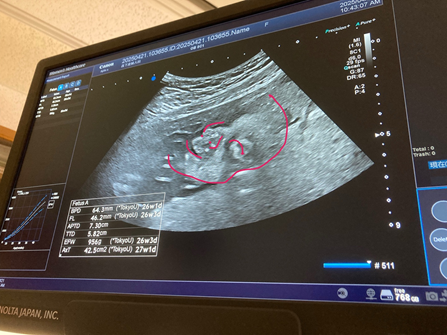

さて、我が家ではパートナーが妊娠6か月を迎えました。

最近、お腹のふくらみもはっきりとわかるようになり、日々成長していく命を間近に感じています。